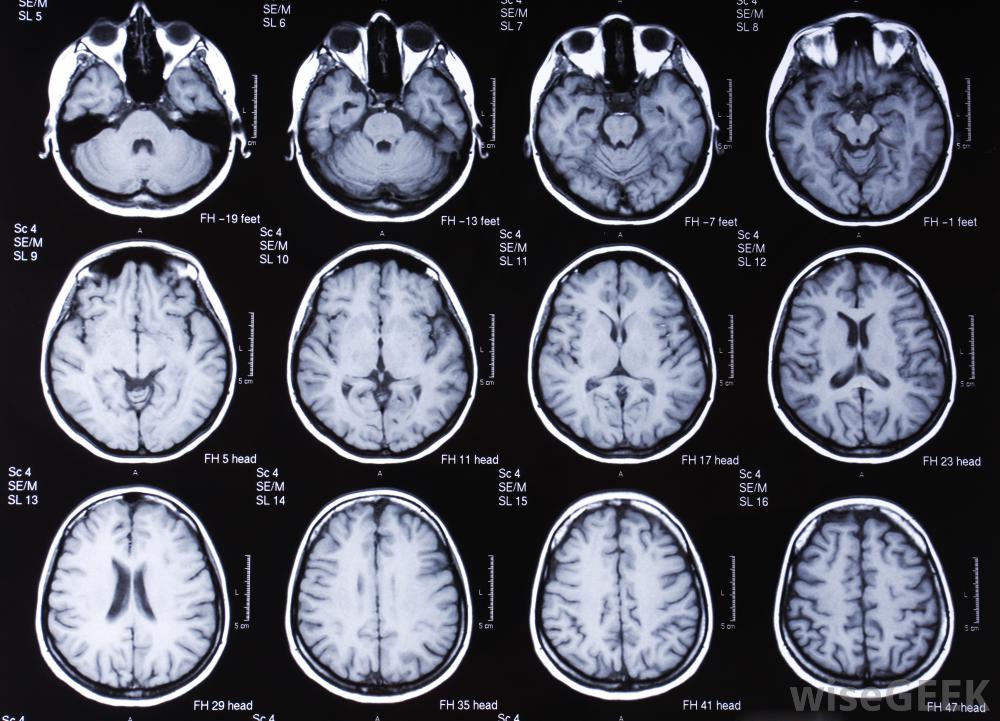

对大脑进行核磁共振扫描。

核磁共振扫描及其无线电波通过重新定位细胞核来改变人体的原子。随着人体原子的移动,任何组织的图像都是由计算机扫描产生的含有少量氢的组织,如骨骼,被视为一个黑暗区域,而拥有最多氢原子的组织,如软组织,则变得更轻。

通过制作各种人体组织的详细图片,核磁共振扫描是发现肿瘤和检查大脑和脊髓的最佳技术之一,MRI扫描已成为确定脑组织异常的最佳技术之一,对于发现心脏缺陷和身体内部器官的其他潜在并发症也非常有效。